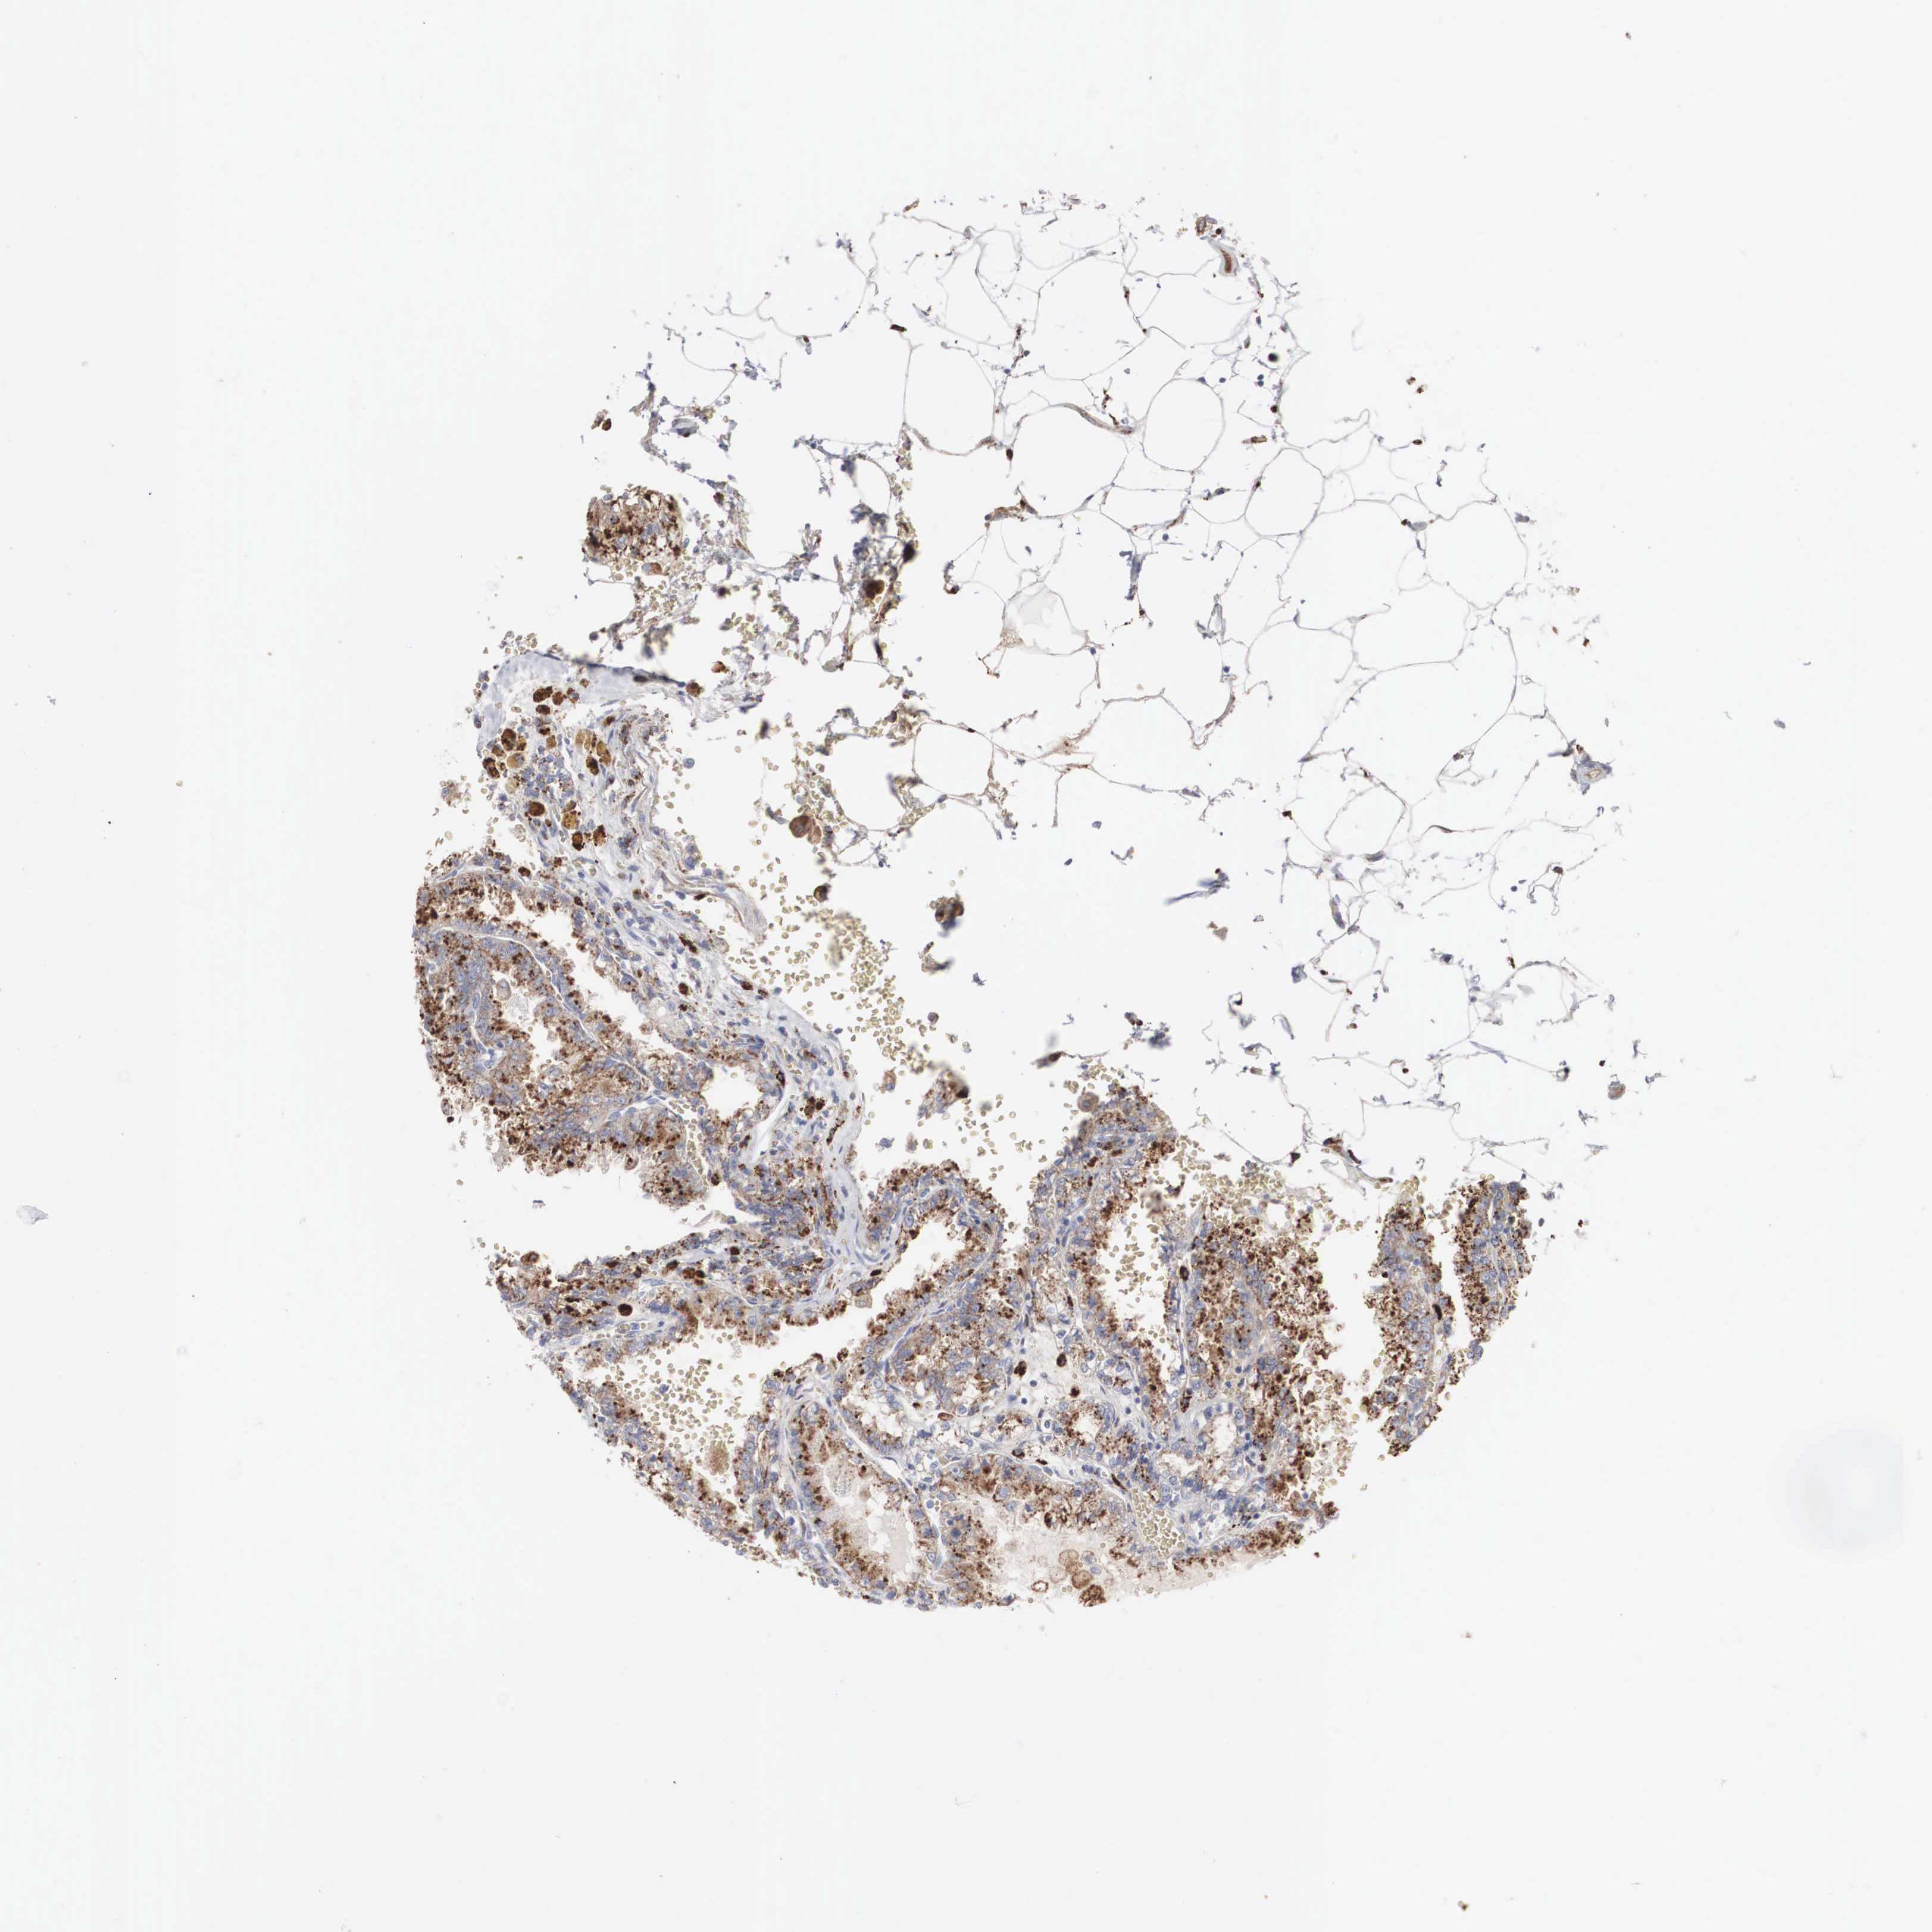

KIDNEY RENAL CLEAR CELL CARCINOMA (VALIDATION) - Interactive survival scatter ploti

The Survival Scatter plot shows the clinical status (i.e. dead or alive) for all individuals in the patient cohort, based on the same data that underlies the corresponding Kaplan-Meier plots. Patients that are alive at last time for follow-up are shown in blue and patients who have died during the study are shown in red.

The x-axis shows the expression levels (FPKM) of the investigated gene in the tumor tissue at the time of diagnosis. The y-axis shows the follow-up time after diagnosis (years). Both axes are complimented with kernel density curves demonstrating the data density over the axes. The top density plot shows the expression levels (FPKM) distribution among dead (red) and alive patients (blue). The right density plot shows the data density of the survived years of dead patients with high and low expression levels respectively, stratified using the cutoff indicated by the vertical dashed line through the Survival Scatter plot. This cutoff is automatically defined based on the FPKM cutoff that minimizes the p-score. The cutoff can be changed by dragging the vertical line or by entering a cutoff value in the square labeled "Current cut-off".

Under the Survival Scatter plot the p-score landscape (black curve; left axis) is shown together with dead median separation (red curve; right axis). Dead median separation is the difference in median mRNA expression between patients who have died with high and low expression, respectively. It is calculated as follows: median FPKM expression of dead patients with high expression - median FPKM expression of dead patients with low expression. This is intended to aid the user in visually exploring custom cutoffs and the associated p-scores and dead median separation.

Individual patient data is displayed and can be filtered by clicking on one or more of the category buttons on the top of the page. Categories describing expression level and patient information include: high, low, alive, dead, female, male and tumor stages. The scale of the x-axis can be toggled between linear and log-scale by clicking on the "x log" button. Mouse-over function shows TCGA ID, patient information and mRNA expression (FPKM) for each patient.

& Survival analysisi

Kaplan-Meier plots summarize results from analysis of correlation between mRNA expression level and patient survival. Patients were divided based on level of expression into one of the two groups "low" (under cut off) or "high" (over cut off). X-axis shows time for survival (years) and y-axis shows the probability of survival, where 1.0 corresponds to 100 percent.

LGALS3BP is validated prognostic, high expression is unfavorable in Kidney Renal Clear Cell Carcinoma (validation)

Best expression cut offi

Based on the FPKM value of each gene, patients were classified into two groups and association between prognosis (survival) and gene expression (FPKM) was examined. The best expression cut-off refers the FPKM value that yields maximal difference with regard to survival between the two groups at the lowest log-rank P-value. Best expression cut-off was selected based on survival analysis .

When clicking on this number, the vertical dashed line indicating cut-off, the interactive survival plot, and the Kaplan-Meier curve will be adjusted to show results based on the best expression cut-off.

: 472.36

Median expressioni

Median expression refers to the median FPKM value calculated based on the gene expression (FPKM) data from all patients in this dataset. When clicking on this number, the vertical dashed line indicating cut-off, the interactive survival plot, and the Kaplan-Meier curve will be adjusted to show results based on the median expression.

: N/A

Median follow up timei

Median follow up time refers to the median time (years) after diagnosis with this type of cancer, based on clinical data from all patients in this dataset.

P scorei

Log-rank P value for Kaplan-Meier plot showing results from analysis of correlation between mRNA expression level and patient survival.

N/A

5-year survival highi

5-year survival for patients with higher expression than the expression cutoff.

For melanoma and glioma, 3-year survival is shown.

5-year survival lowi

5-year survival for patients with lower expression than the expression cutoff.

TCGA RNA samplesi

RNA-seq data is reported as average FPKM (number Fragments Per Kilobase of exon per Million reads), generated by the The Cancer Genome Atlas (TCGA) .

Normal distribution across the dataset is visualized with box plots, shown as median and 25th and 75th percentiles. Points are displayed as outliers if they are above or below 1.5 times the interquartile range. FPKM values of the individual samples are presented next to the box plot.

Average pTPM 356.9

Number of samples 100